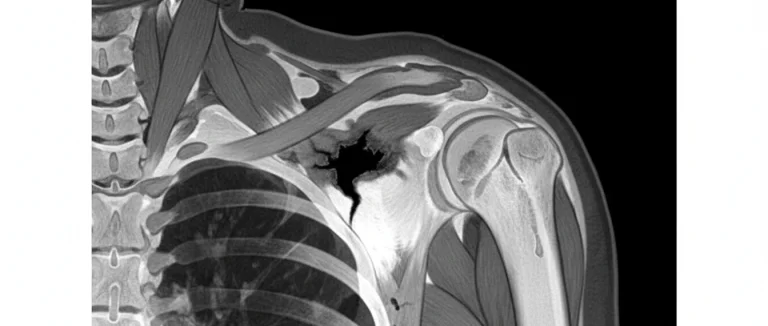

Точная диагностика является фундаментом эффективного лечения разрыва сухожилия надостной мышцы. Врач‑ортопед обычно начинает с клинического осмотра и специальных тестов, таких как тест «drop arm», который позволяет оценить целостность сухожилия.

Для подтверждения диагноза применяются современные визуализационные техники:

| MRI (магнитно-резонансная томография) | Высокая чувствительность к мягким тканям, детальная визуализация разрыва | Стоимость, необходимость в магнитном поле |

| CT (компьютерная томография) | Хороша для оценки костных структур, если подозревается сопутствующий перелом | Низкая информативность по мягким тканям |

В большинстве случаев MRI считается золотым стандартом для оценки степени разрыва, наличия отека и сопутствующих повреждений. При необходимости врач может дополнительно назначить артроскопию для прямой визуализации и возможного одновременного лечения.